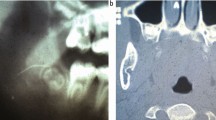

This article presents a distant complication in the auricle following the administration of a standard inferior alveolar nerve block. The patient experienced profound numbness of the auricle on the ipsilateral side of the injection that lasted for about an hour following unintended injection to the auriculotemporal nerve.